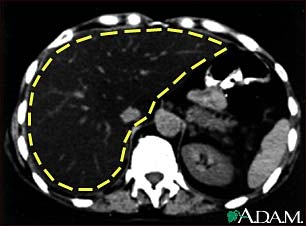

Liver fattening, CT scan

A CT scan of the upper abdomen showing a fatty liver (steatosis of the liver). Note the liver enlargement and dark color compared with the spleen (gray body in lower right).